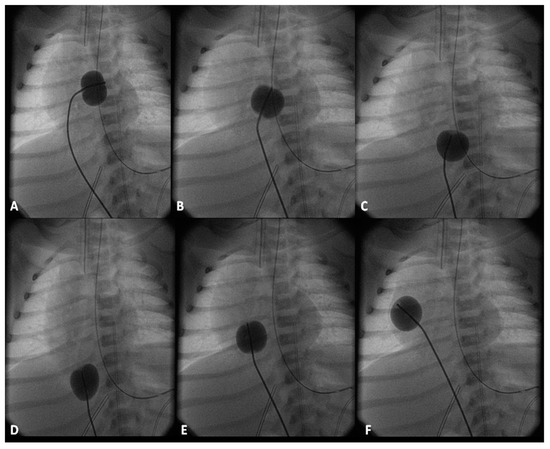

7.3.3. Ensure Adequate Egress of the Left Atrial Blood

The left atrial blood must egress into the right atrium, across the PFO, because of the obstructed mitral valve/LV. In some infants, the PFO may be small at birth or may become restrictive with time. Mild degree of narrowing may be beneficial in that it will increase the PVR which in turn may help adequate systemic flow. However, severe restriction produces pulmonary edema with consequent hypoxemia. Consequently, it is important to perform periodic echo-Doppler studies in order to monitor the size of the PFO and the degree of restriction. When the obstruction becomes severe, enlargement of the PFO by trans-catheter techniques [41,42,43,70] should be performed. While Rashkind’s balloon atrial septostomy [41] and Park’s blade septostomy [43,70] are conventional methods to lessen atrial septal obstruction, such techniques are not easy to perform because of the hypoplastic left atrium. Static balloon dilatation of the atrial septum [42,102,103] with a balloon angioplasty catheter (Figure 12) is useful. Such a procedure may not only help relieve severe obstruction, but also retain a mild degree of obstruction so that rapid fall in the PVR does not occur. Rarely, the obstruction is extremely severe and may require stent implantation [42,104].